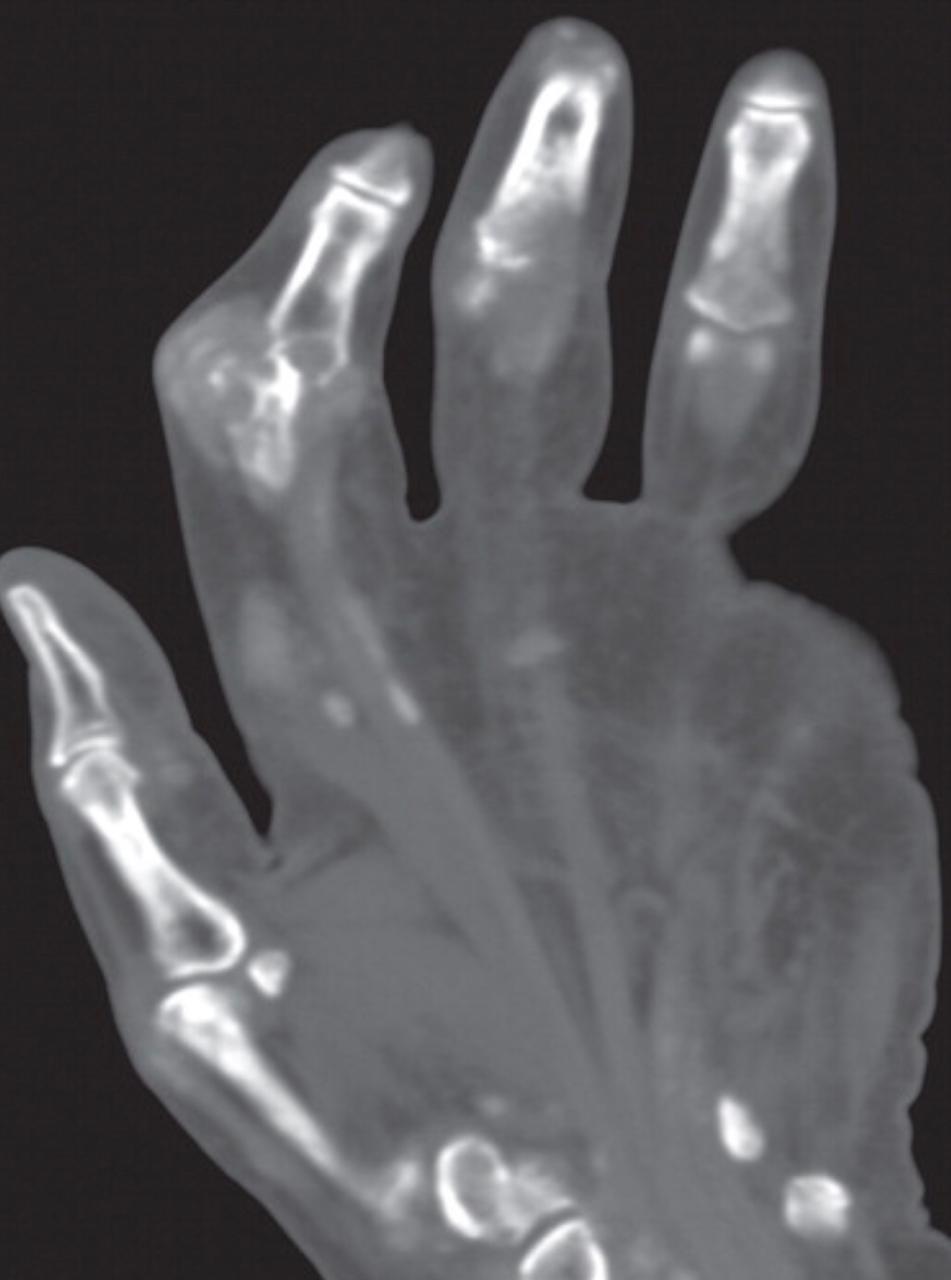

Although diagnosing gout generally is straightforward, atypical disease may present a challenge if it is associated with unusual symptoms or sites, discordant serum urate level, or mimics of gout. Dual-energy computed tomography (CT) may be used to differentiate urate crystals from calcium by using specific attenuation characteristics, which may help diagnose gout. In patients with known tophaceous gout, dual-energy CT may be used for serial volumetric quantification of subclinical tophi to evaluate response to treatment.

Dual-energy CT can quantitatively identify monosodium urate crystal deposits with high sensitivity and specificity within joints, tendons, and periarticular soft tissues.

Given the utility of dual-energy CT in challenging cases and its ability to provide an objective outcomes measure in patients with tophaceous gout, dual-energy CT promises to be a unique and clinically relevant modality in the diagnosis and management of gout.